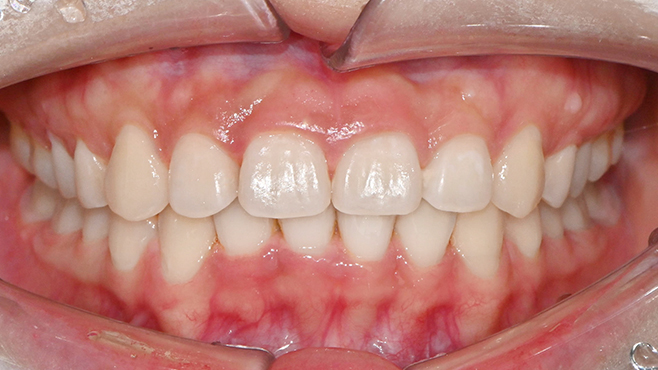

맞는 건 괜찮은데… 충치는 못 참겠습니다|20대 격투기 선수 치과 방문기